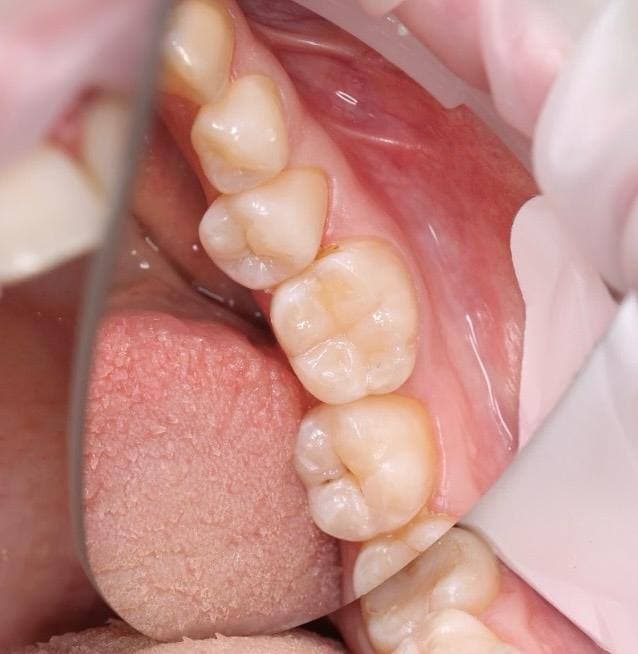

Восстановление зуба пломбой с нарушением контактного пункта (с использованием материалов из фотополимеров II, III класса)